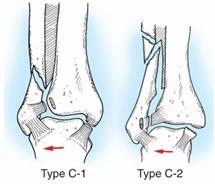

Рисунок 1 Типы переломов лодыжек

Переломы лодыжек возникают в основном при непрямой травме, причем важнейшее значение имеют боковые и ротационные движения. При подвертывании стопы кнаружи или кнутри происходят чрезмерные, выходящие за пределы физиологической возможности движения, которые приводят к разрыву связок голеностопного сустава или перелому костей. При подвертывании стопы, как правило, возникают и ротационные движения голени вокруг оси при фиксированной стопе.